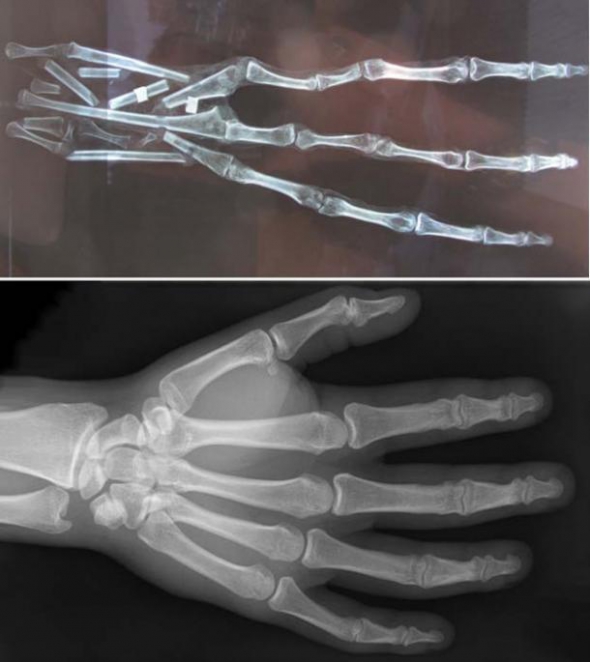

В Перу ученые нашли мумифицированную руку с тремя 20-ти см пальцами.

Руку нашли в пустыне. В туннели, где инки хоронили людей. Местный врач изучил ее. Каждый палец состоит из 6 костей. Также на руке есть кожа. Это доказывает, что мумия не искусственная.

Биологи утверждают, что находка явно не является частью тела животного.

Ученые не могут сказать, кому принадлежит эта рука. Предполагают, что она может быть остатком неизвестного человекоподобного вида. В этом году археологи хотят провести ДНК-анализ руки.